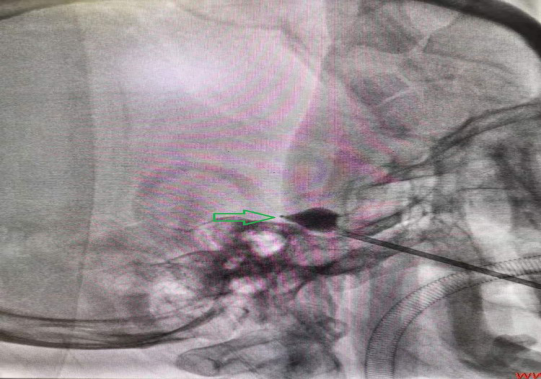

球囊位置向梨尖处轻微扩展(绿色箭头)。特征性的梨状外观表明球囊进入Meckel´s腔。